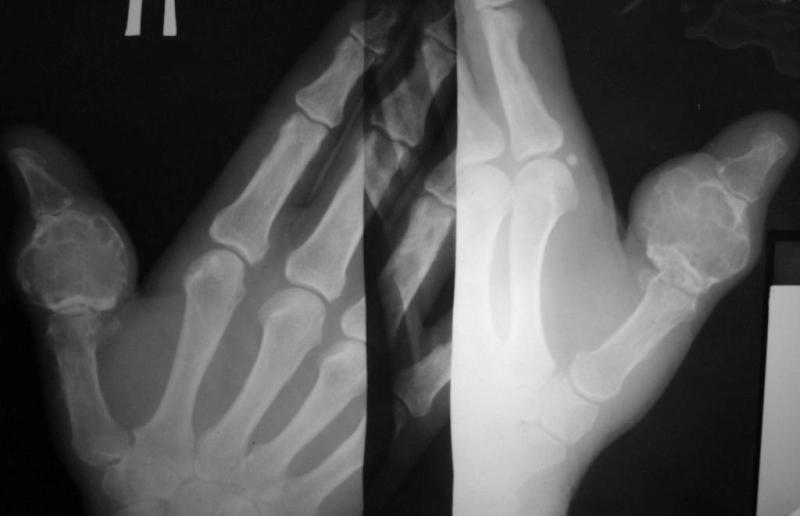

Больная, 68 лет. 10 лет назад со слов больной была трвма пальца, за помощью не обращалась, была

небольшая припухлость. За последние 2 года отметила рост опухолеподобного образования,

появились боли, ограничение движений 1 пальца. При пальпации умеренная болезненость.

Наблюдалась в поликлинике по месту жительства с диагнозами - солитарная костная киста,

энхондрома. Госпитализирована с диагнозом остеобластокластома проксимальной фаланги 1

пальца правой кисти.

Предлагается удаление проксимальной фаланги и костная пластика:

1. трансплантатом из гребня подвздошной кости

2. трансплантатом из большеберцовой кости

3.трансплантатом из головки плюсневой кости